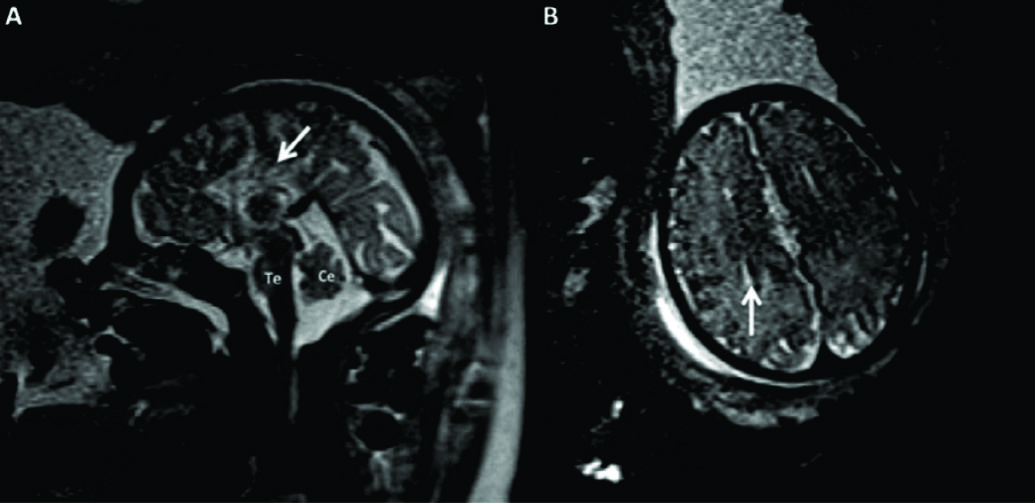

Figura 13

Correlación entre NSF y RMf en malformaciones.

Correlación entre hallazgos ecográficos y RMf en un feto con estudio ecográfico por via abdominal (A) y trans-vaginal (NSF) (B). Se observa solución de continuidad a nivel de la región occipital con contenido meníngeo, sin herniación de parénquima encefálic,o (è). Esto se confirma mediante RMf (C) corte axial; D: corte sagital) lo que establece el diagnóstico de meningocele occipital. CSP: cavum septum pellucidum

V: vermis cerebeloso

Te: tronco encefálico

Figura 14

Correlación entre cortes sagitales de NSF y RMf . Se muestra el caso de un feto con trombosis venosa a nivel de la tórcula y dilatación del seno longitudinal superior.

En las figuras A y B se puede ver el trombo ecogénico (è) y la dilatación del seno sagital hipoecogénico (*), el cual comprime y desplaza las estructuras encefálicas. La RMf realizada unos días después confirma los hallazgos mostrando una trombosis sub-aguda en topografía de la tórcula (è), asociada a dilatación del seno longitudinal (C). Luego el feto sufre una hemorragia intraventricular como se muestra en la figura D (**).

C: Cerebelo